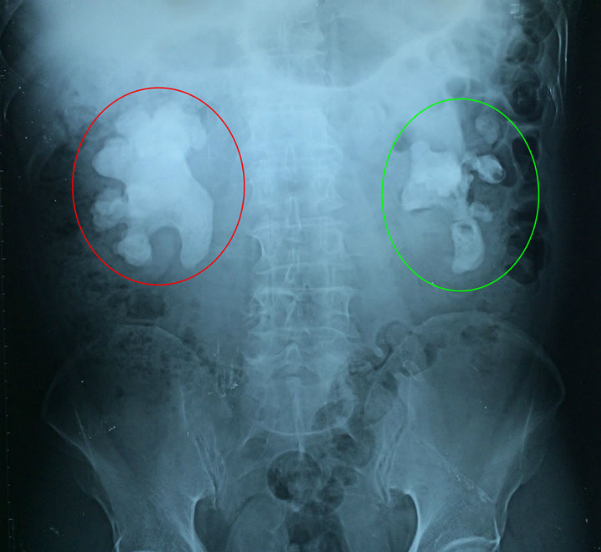

Đau bụng dữ dội, đi tiểu có lẫn máu, cụ ông ở Quảng Ninh, 71 tuổi đi cấp cứu vào bệnh viện. Sau khi chiếu soi thì bệnh viện phát hiện trong thận của cụ có một khối sỏi san hô lớn lạ kỳ.

Các bác sĩ Bệnh viện Việt Nam - Thụy Điển Uông Bí kết hợp với bác sĩ Bệnh viện Việt Đức vừa tiến hành phẫu thuật thành công lấy bỏ khối sỏi san hô kích thước 6 x 9 cm ra khỏi thận bên phải cho cụ ông.

Theo các bác sĩ, đây là một trường hợp phức tạp khi sỏi san hô ở cả 2 bên, hiếm gặp. Sỏi to lấp đầy toàn bộ các nhóm đài bể thận. Nếu không điều trị sỏi sẽ tàn phá làm mất chức năng thận, gây ra những đợt nhiễm trùng thận tái đi tái lại, đôi khi nhiễm trùng nặng có thể gây nguy hiểm tính mạng của người bệnh.

Bệnh nhân sẽ được phẫu thuật lấy sỏi thận bên trái sau khi ổn định sức khoẻ. Ảnh: Bệnh viện cung cấp.

Hiện, sau phẫu thuật, sức khỏe người bệnh ổn định, dẫn lưu vùng mổ đã hết dịch, nước tiểu trong. Sau khi sức khỏe người bệnh ổn định sẽ được tiến hành phẫu thuật lấy bỏ khối sỏi san hô tại thận bên trái.